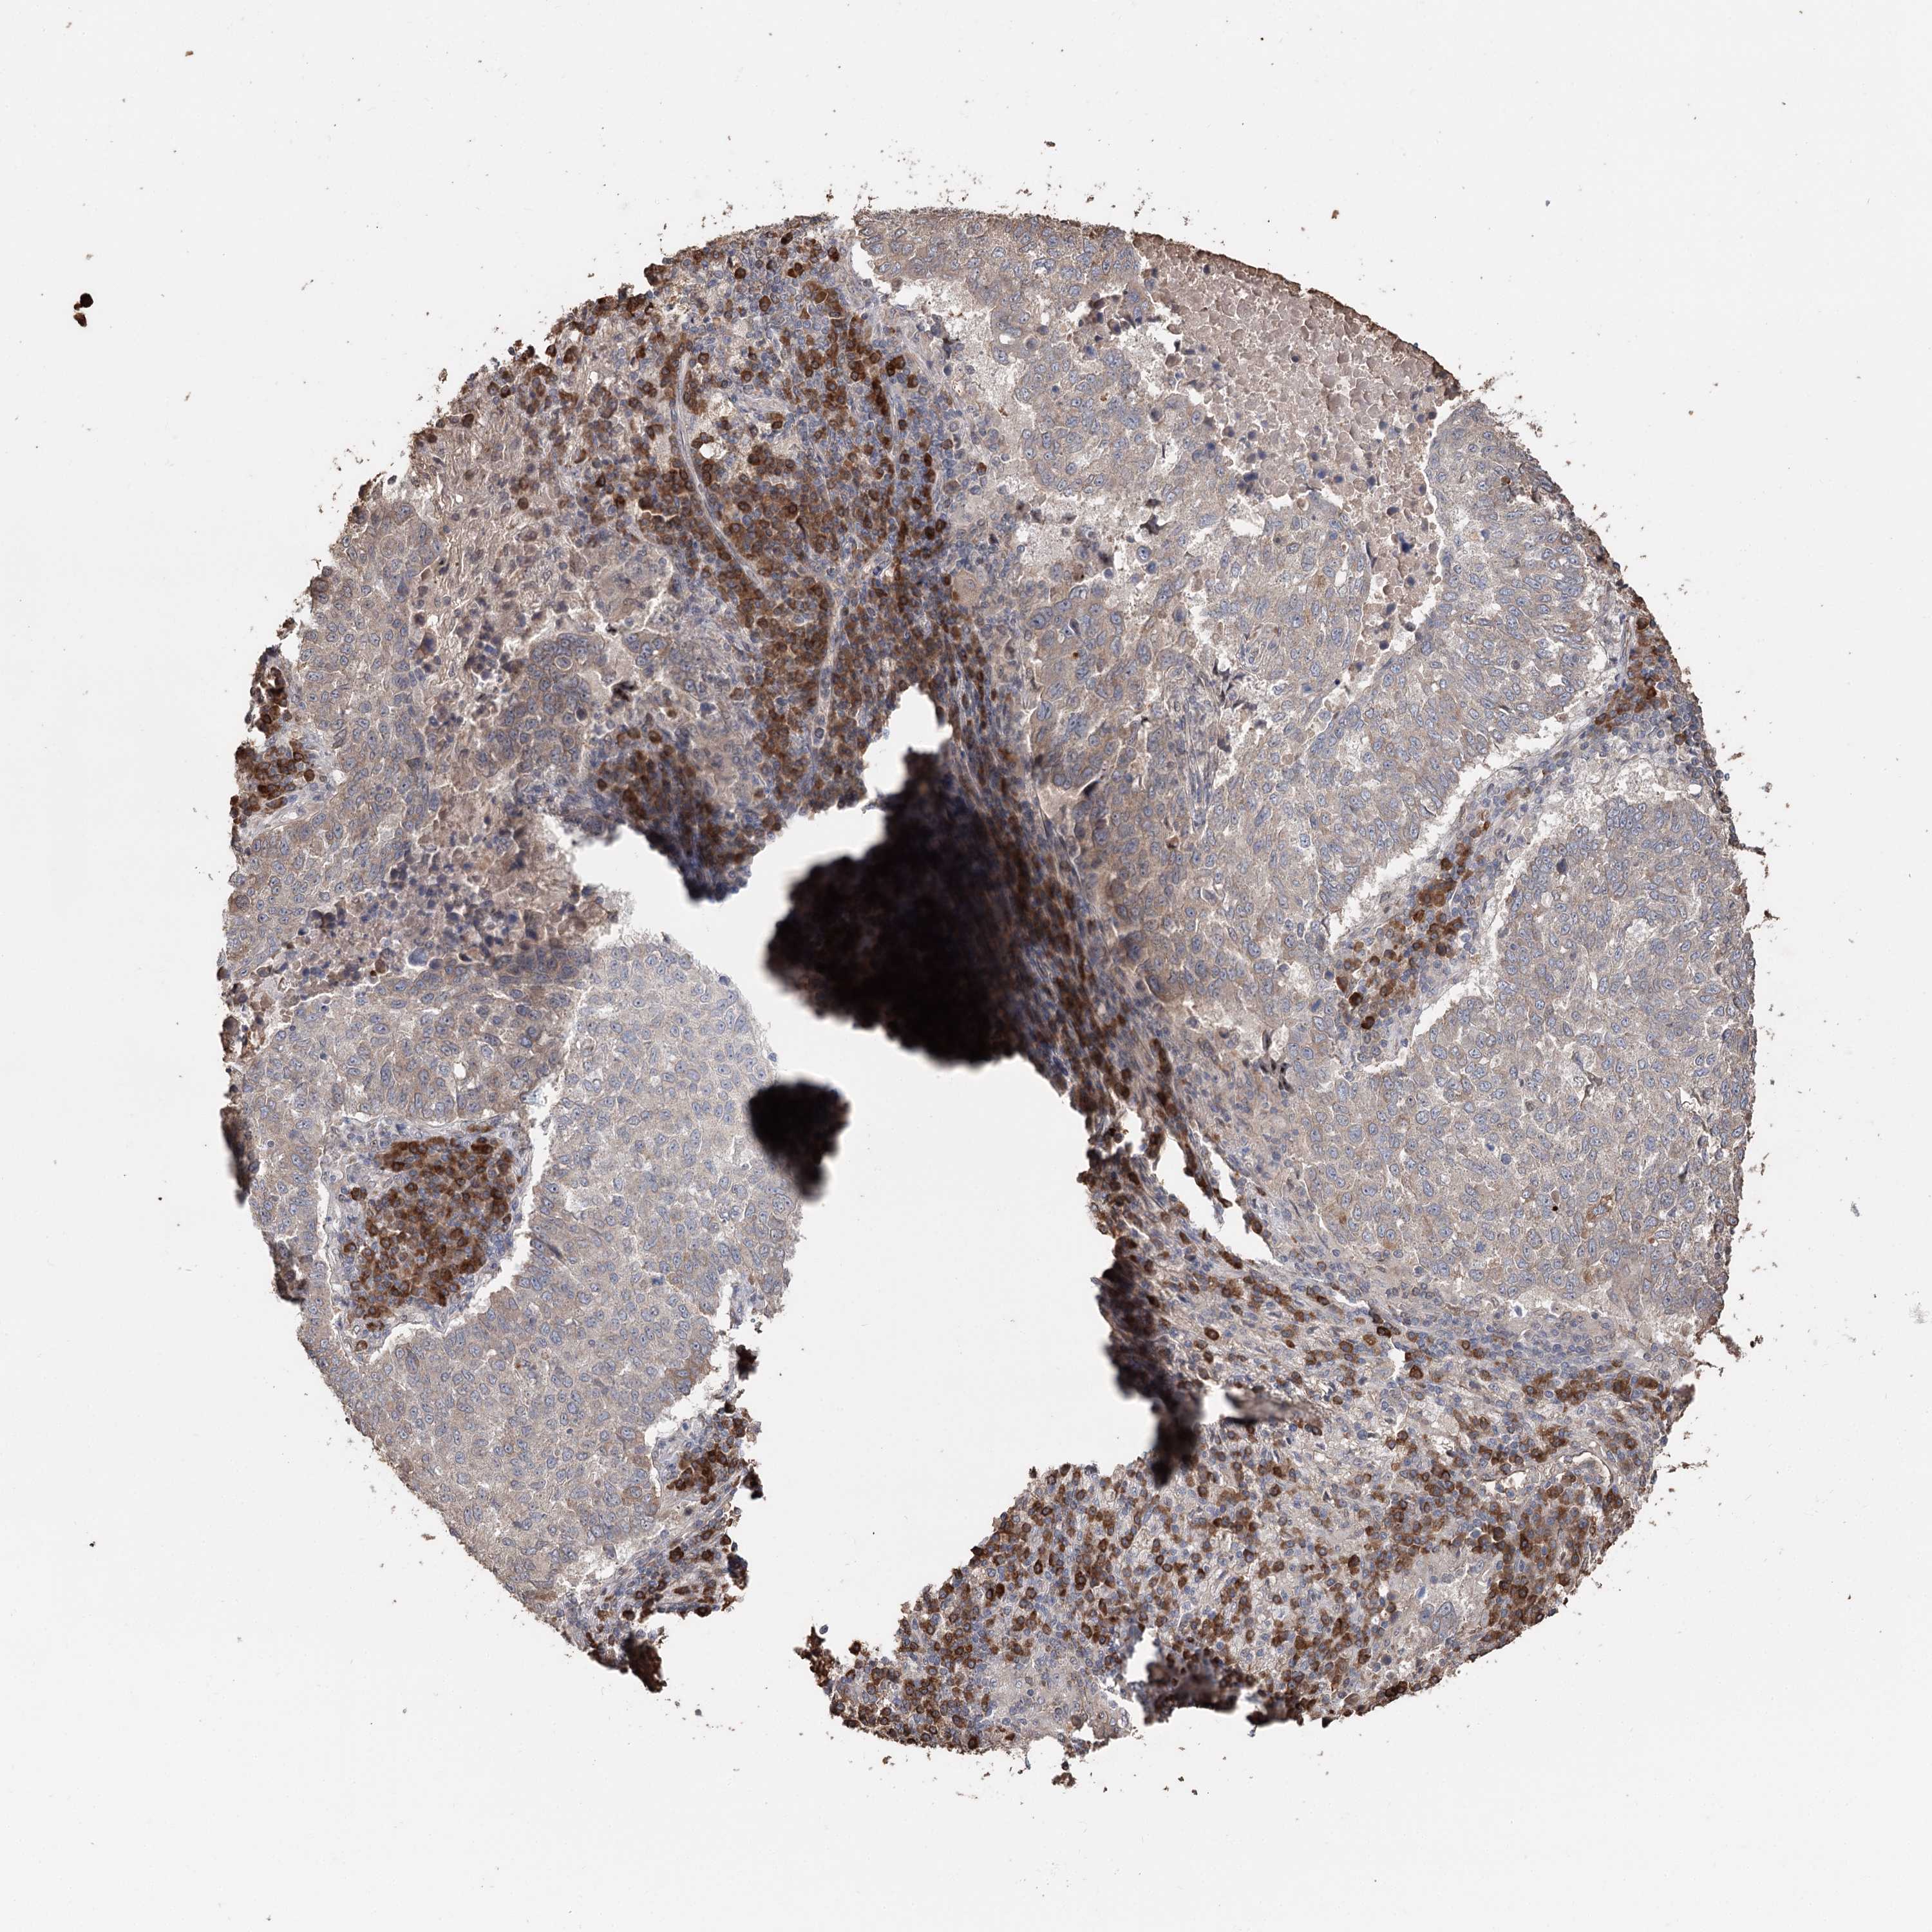

LUNG SQUAMOUS CELL CARCINOMA (TCGA) - Interactive survival scatter ploti

The Survival Scatter plot shows the clinical status (i.e. dead or alive) for all individuals in the patient cohort, based on the same data that underlies the corresponding Kaplan-Meier plots. Patients that are alive at last time for follow-up are shown in blue and patients who have died during the study are shown in red.

The x-axis shows the expression levels (FPKM) of the investigated gene in the tumor tissue at the time of diagnosis. The y-axis shows the follow-up time after diagnosis (years). Both axes are complimented with kernel density curves demonstrating the data density over the axes. The top density plot shows the expression levels (FPKM) distribution among dead (red) and alive patients (blue). The right density plot shows the data density of the survived years of dead patients with high and low expression levels respectively, stratified using the cutoff indicated by the vertical dashed line through the Survival Scatter plot. This cutoff is automatically defined based on the FPKM cutoff that minimizes the p-score. The cutoff can be changed by dragging the vertical line or by entering a cutoff value in the square labeled "Current cut-off".

Under the Survival Scatter plot the p-score landscape (black curve; left axis) is shown together with dead median separation (red curve; right axis). Dead median separation is the difference in median mRNA expression between patients who have died with high and low expression, respectively. It is calculated as follows: median FPKM expression of dead patients with high expression - median FPKM expression of dead patients with low expression. This is intended to aid the user in visually exploring custom cutoffs and the associated p-scores and dead median separation.

Individual patient data is displayed and can be filtered by clicking on one or more of the category buttons on the top of the page. Categories describing expression level and patient information include: high, low, alive, dead, female, male and tumor stages. The scale of the x-axis can be toggled between linear and log-scale by clicking on the "x log" button. Mouse-over function shows TCGA ID, patient information and mRNA expression (FPKM) for each patient.

& Survival analysisi

Kaplan-Meier plots summarize results from analysis of correlation between mRNA expression level and patient survival. Patients were divided based on level of expression into one of the two groups "low" (under cut off) or "high" (over cut off). X-axis shows time for survival (years) and y-axis shows the probability of survival, where 1.0 corresponds to 100 percent.

SYVN1 is not prognostic in Lung Squamous Cell Carcinoma (TCGA)

: 34.2